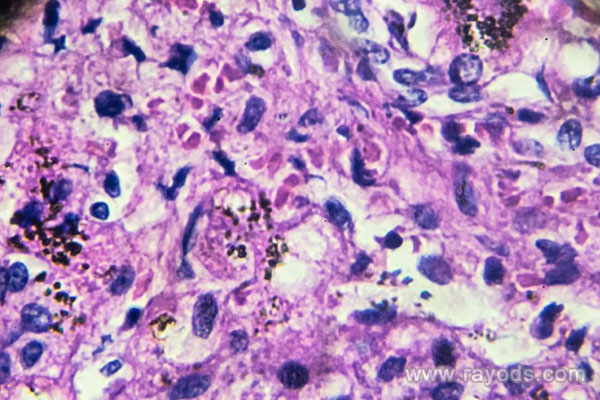

患者会感觉外阴发痒等,有些患者会出现阴道分泌物增多的情况,分泌物中含有菌丝体等,状如凝乳或豆腐渣,比较浓稠,颜色发白。当患者排尿的时候,尿液刺激到外阴和前庭会让患者感觉到疼痛。通过检查会发现患者外阴发红、有抓痕等。如果病情比较严重,患者的皮肤还会龟裂。此外会发现患者的小***粘膜红肿不堪,且会分泌白色物质。如果正处于急性期,阴道会有糜烂、溃疡情况。